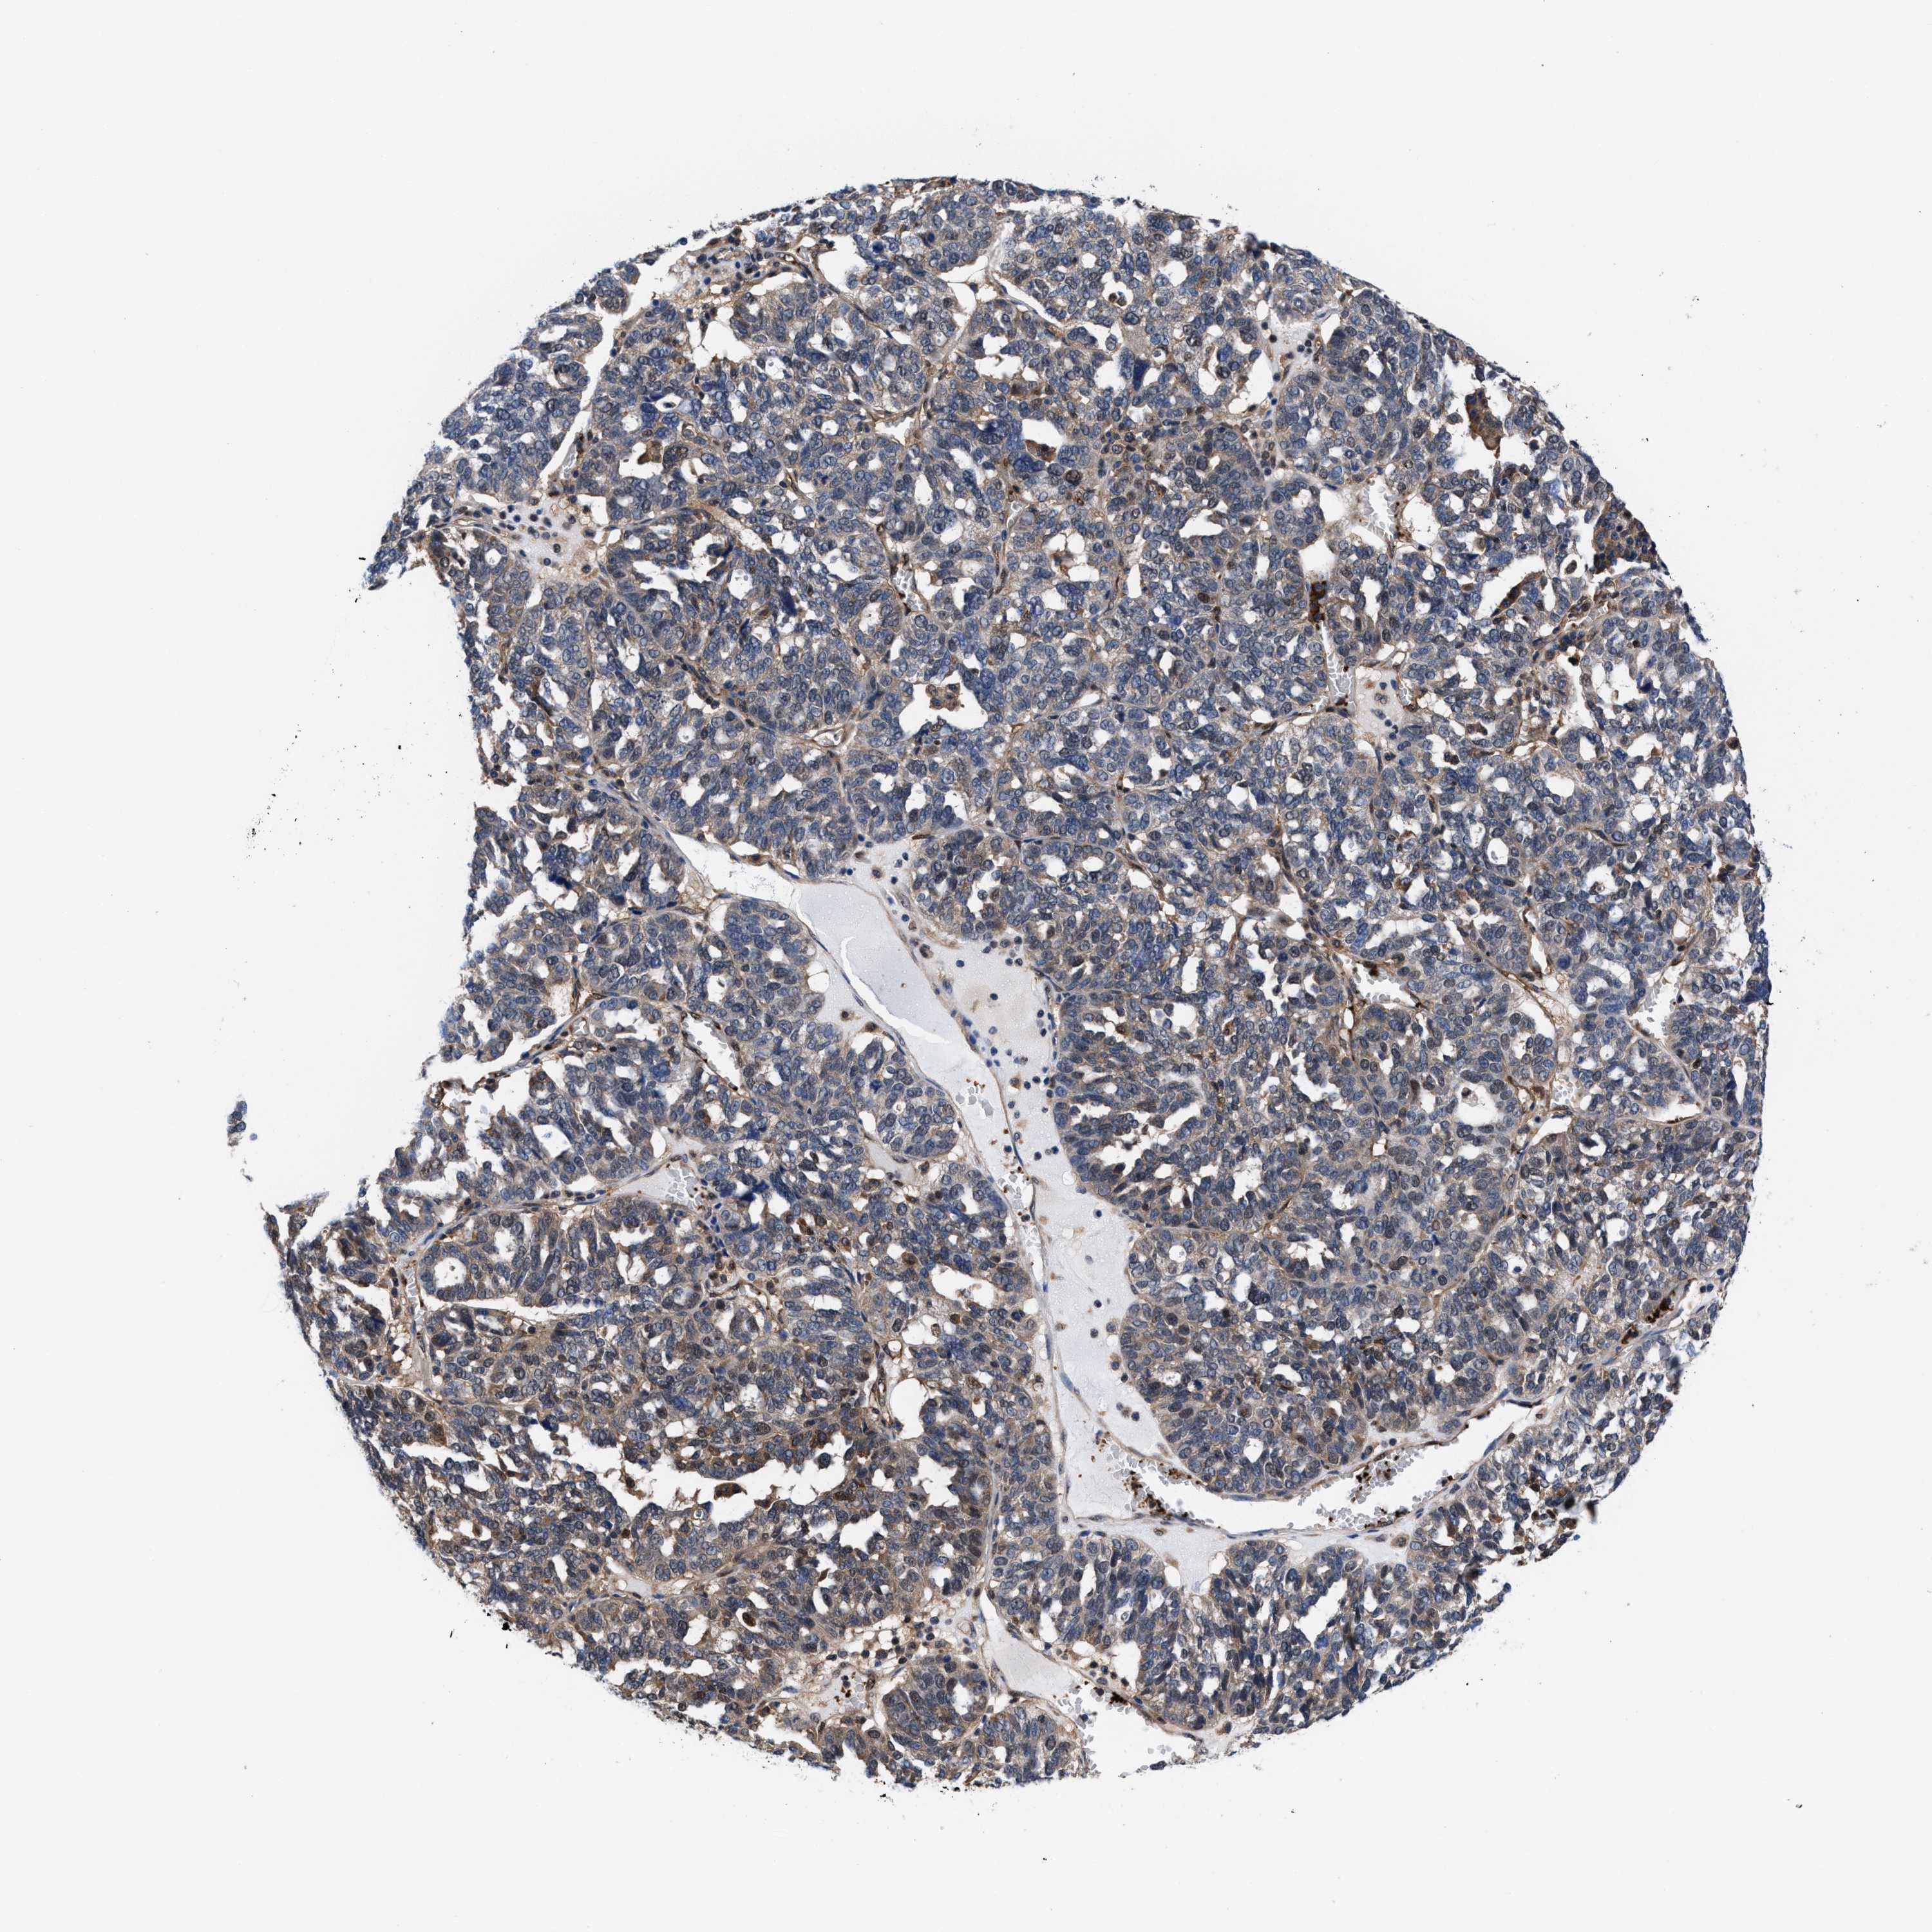

OVARIAN CANCER - Protein expressioni

A mouse-over function shows sample information and annotation data. Click on an image to view it in a full screen mode. Samples can be filtered based on level of antibody staining by selecting one or several of the following categories: high, medium, low and not detected. The assay and annotation is described here.

Note that samples used for immunohistochemistry by the Human Protein Atlas do not correspond to samples in the TCGA dataset.

Antibody stainingi

Antibody staining in the annotated cell types in the current human tissue is reported as not detected, low, medium, or high, based on conventional immunohistochemistry profiling in selected tissues. This score is based on the combination of the staining intensity and fraction of stained cells.

Each image is clickable and will lead to virtual microscopy that enables deeper exploration of all samples and also displays staining intensity scores, fraction scores and subcellular localization as well as patient and tissue information for each sample.

HPA022434

HPA022953

HPA022959

HPA028758

CAB007783

Staining

High

Medium

Low

Not detected

Intensity

Strong

Moderate

Weak

Negative

Quantity

>75%

75%-25%

<25%

None

Location

Nuclear

Cytoplasmic/membranous

Cytoplasmic/membranous,nuclear

Cystadenocarcinoma, serous, NOS

Carcinoma, endometroid

Cystadenocarcinoma, mucinous, NOS

Carcinoma, NOS